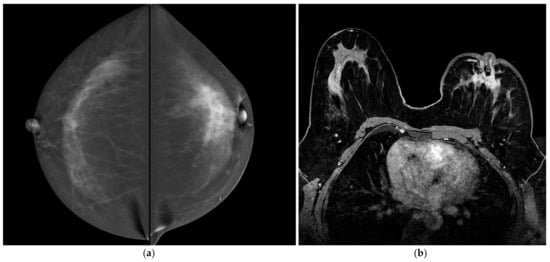

According to MRI-BI-RADS lexicon, the internal enhancement pattern of non-mass lesions includes homogeneous, heterogeneous, clumped and clustered rings [46]. These descriptors are hard to apply in CESM (Figure 5 and Figure 6).

Figure 6.

A 44-year-old women with large CLI of the left breast. Patient performs mammography because of a nipple retraction of the left breast. (a) CESM CC views show non-mass pathological enhancement on the left breast extending to the nipple. (b) Axial post-contrast T1-weighted fat saturation dynamic sequence (Vibrant) shows homogeneous non-mass enhancement consistent with classic CLI (T2, N1, M0, ER 90%, PgR 85%, Ki67 35%, G2). Pathological enhancement reaches the nipple. In right breast, BMR shows marked homogenous enhancement of the parenchyma of the external quadrants, that is not visible in CESM. Core needle biopsy was performed to confirm the absence of bilateral disease.

These difficulties in evaluating some specific descriptors seems to make CESM examination less accurate. However, we adapted the lexicon created for MRI and used it for CESM, thus a new specific CESM lexicon should probably be promoted.